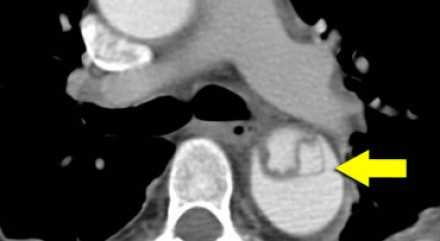

- На ниже лежащих снимках представлен пациент с диссекцией типом B. Истинный просвет окружен кальцификацией. Истинный просвет узкий и подвергается компрессионным изменениям, обусловленных систолическим давлением.

- При диссекции аорты интима визуализируется по старым данным только в 70% случаев, но связи с развитием техники данный показатель на сегодняшний день составляет выше 90%.

- На ниже представленных изображениях представлена диссекция типа B.

- Истинный просвет, окружен кальцификатами.

- Истинный просвет уже, чем ложный просвет, а также четко визуализируется симптом клюва.

- В ложном просвете локализован тромб, который контрастируется позже истинного просвета.

Истинный просвет

- Как правило:

- Окружен кальцификацией.

- Меньше, чем ложный просвет.

- Частая локализация чревный ствол, передняя мезентариальная артерия и правая почечная артерия.

Ложный просвет

- Есть окклюзия тромбом или нет.

- Замедленное контрастирование.

- Шире, чем истинный просвет.

- Имеет круговую конфигурацию

- Симптом клюва.

- Окружает истинный просвет при диссекции типа А